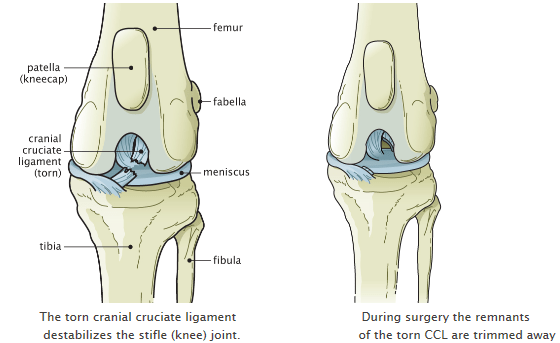

Reconstruction will release tight tissues and tighten loose tissues. The longer the patella. Risks of delaying luxating patella surgery. So second vote for surgery. Also the abnormal pull of the quadriceps causes internal rotation of the tibia relative to the femur that can stress other structures within the knee including the cranial cruciate ligament CCL.